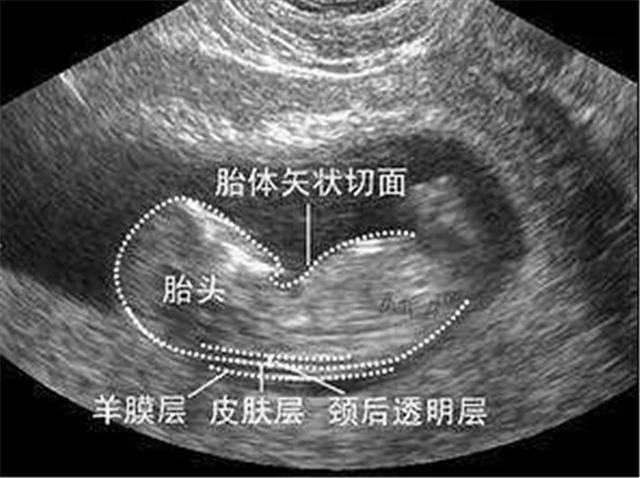

胎儿头脸部

胎儿面部

胎头位于耻骨上,头骨光环光整,脑中线居中,胎儿上唇,鼻骨可预示,生男孩。